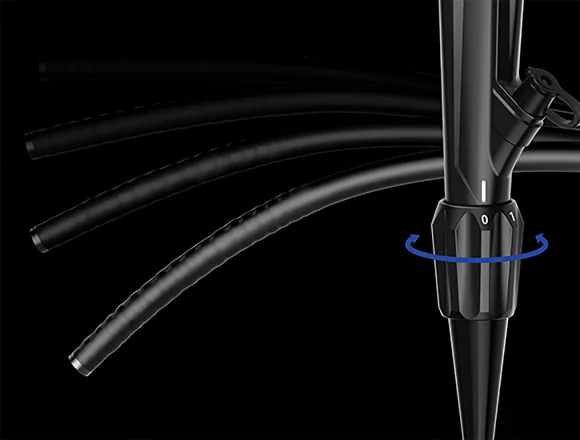

Регулируемая жесткость

Вводная трубка колоноскопа имеет функцию многоуровневой регулировки мягкости и жесткости.Вращая регулировочное кольцо, можно изменять мягкость и твердость вводимой части в соответствии с требованиями эндоскопии различных отделов толстой кишки, как того требуют врачи-клиницисты.